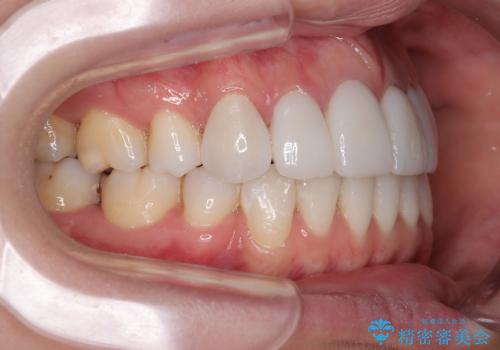

上顎前歯4本は、以前むし歯により神経をすべて取り除かれており、その影響で既に変色を起こしている状態でした。

4本とも歯根部先端の骨が炎症により吸収していることがレントゲン写真から示唆されたため、矯正治療後に4本を再根管治療し、その後上顎6歯をオールセラミッククラウンにて補綴治療することとしました。

歯並びだけでなく、歯の色も明るくなり、すっきりとした口元の印象となりました。